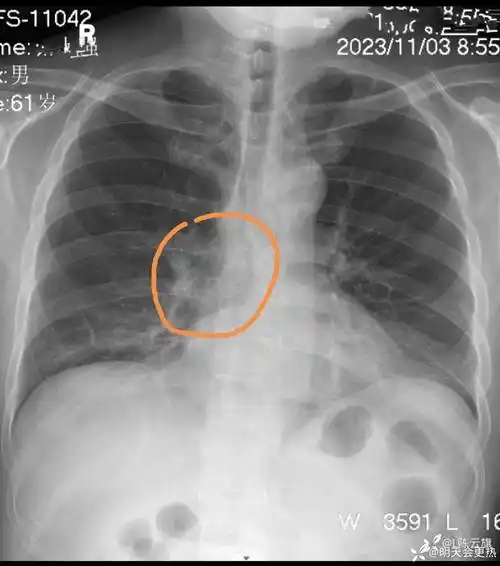

每周胸片203无症状正侧位胸片练练眼力